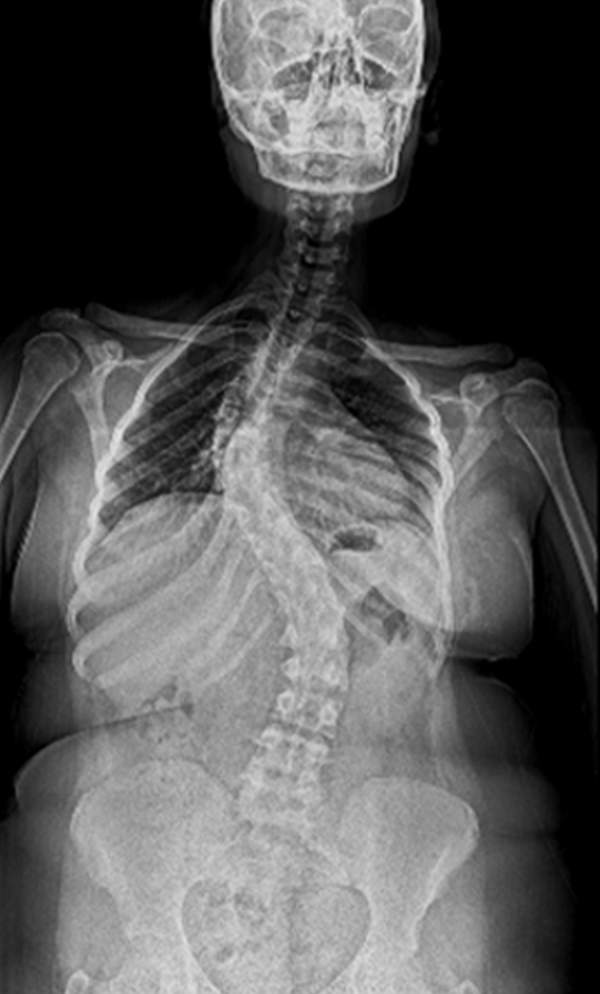

BEYOND RECOVERY : REAL STORIES

Gallery : Before - After